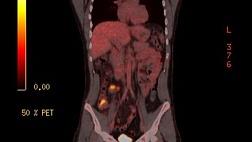

Лекция «Комплексная эндоскопическая диагностика рака легкого опыт НМИЦ онкологии им Н.Н. Блохина Минздрава России»

Л.В. Черкес, М.А. Крыловецкая, Р.С. Савосин

Демонстрация клинического случая: Трансбронхиальная пункция опухоли и лимфатических узлов средостенья

Л.В. Черкес

10:30 – 11:15

Демонстрация клинического случая: Транспищеводная пункция опухоли и лимфатических узлов средостенья

Демонстрация клинического случая: Криобиопсия рака легкого

И.В. Сивокозов